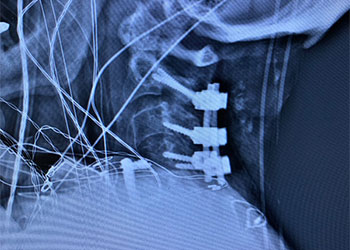

Revision Surgery Treats Intractable Neck Pain & Cervical Deformity

Author: Benjamin R. Cohen M.D., F.A.A.N.S., F.A.C.S., Read More!